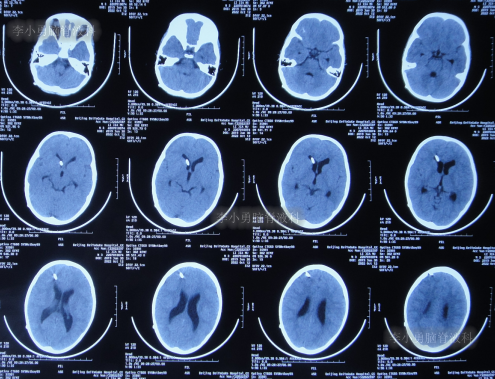

2022年10月19日(住院治疗111天),拔除了脑室引流术,拔管前和拔管后头颅CT(图-18)对比。

图-18:2022年10月19日拔管前后头颅CT对比

2022年10月25日(李小勇脑脊液科治疗117天),出院时:精神状态挺好,大小便正常,虽右腿走路稍差但走路速度变快,变稳(图-19);出院时头颅CT示未见异常(图-20)。

图-20:出院时头颅CT